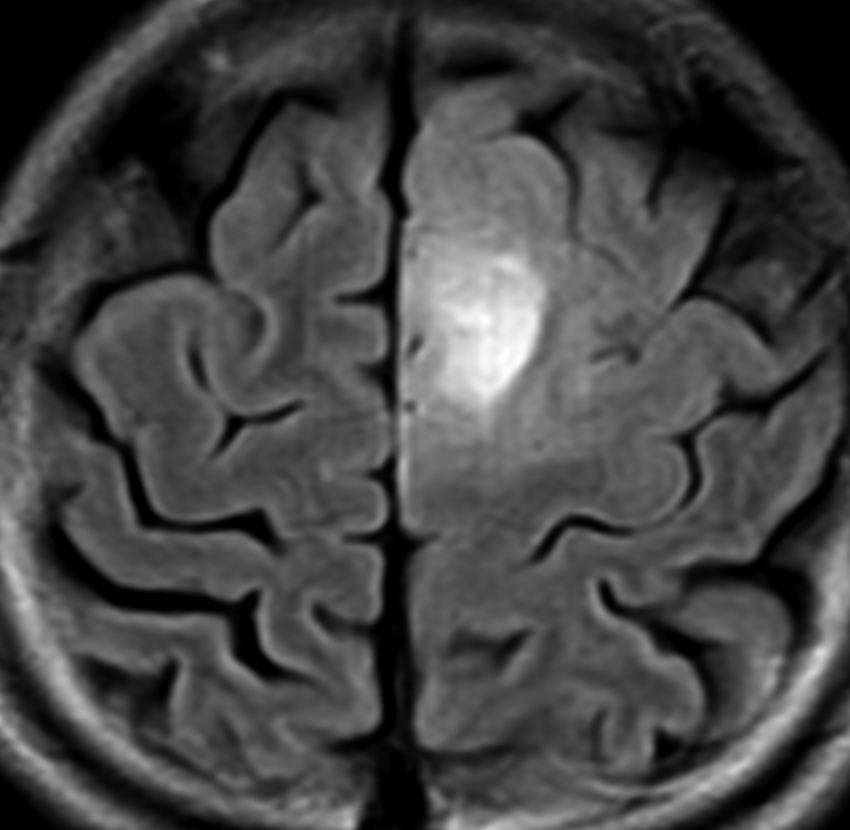

悪性転化 malignant transformation,膠芽腫への進展 progression

40代の患者さんです。夜間睡眠中の全般発作(症候性てんかん)で発症しました。フレア画像で左上前頭回に滲むような高信号領域(白い部分)がみられます。右側はガドリニウム増強MRIですが,全く増強されません。グレード2か3の星細胞腫あるいは乏突起膠腫を疑います。白く滲むような領域はよく見るとかなり広範囲に広がっています。